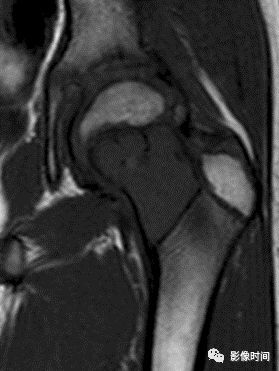

肿瘤对骨骺板和关节软骨的破坏是对骨破坏的继续。缺乏血管的骨骺板对恶性肿瘤有抵抗作用,骨骺板可暂时阻止肿瘤的蔓延,但当肿瘤进一步发展时, 骨骺板亦可被破坏,X 线平片或 CT 可表现为先期钙化带密度减低、中断或消失。MRI 可显示肿瘤从干骺端跨越骨骺板侵犯骨骺(图 15、图 16)。

肿瘤突破关节软骨向关节腔发展时, 可表现为关节面破坏、塌陷(图 17), 关节腔内出现软组织肿块。少数良性骨肿瘤如软骨母细胞瘤, 亦可超越骺板向两侧发展或突入关节腔内, 此为肿瘤膨胀生长所致, 而非浸润性破坏。

图 15  骨骺板破坏:骨肉瘤

图 16  骨骺板破坏:骨肉瘤

图 17  关节软骨破坏:骨肉瘤